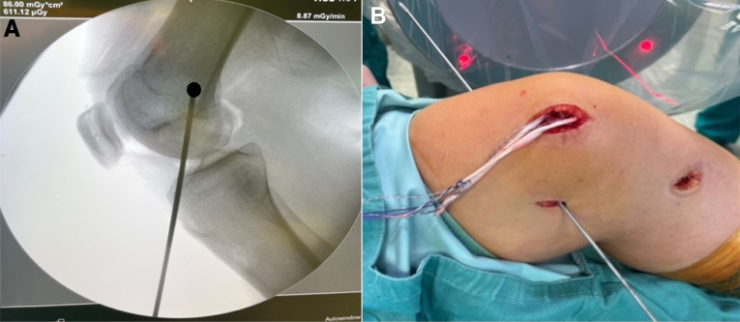

⑥然后,在透视下采用Schöttle技术,在导丝引导下于内收肌结节(AT)和股骨内上髁(MEC)中点前方的等长点处制作一个7毫米的骨隧道。等长点是在标准侧位平面上确定的,位于Blumensaat线后端点水平的近端、后皮质延长线前方1毫米处,以及股骨内侧髁后缘起点远端2.5毫米处。

图6:影像增强器显示的等长点视图(由箭头标记),该点位于内收肌结节和股骨内上髁之间。采用舍特勒(Schöttle)技术时,在此处钻入导丝以制作骨隧道,以便让移植物穿过。

⑦将移植物从股内侧斜肌下方穿过,并经预先制备好的隧道拉入股骨内。将髌骨保持在滑车外侧缘处,在施加适当张力的情况下,在膝关节30°屈曲位、足部处于中立旋转位时,使用一枚7毫米×25毫米的RCI金属干涉螺钉固定移植物。

图7:通过透视检查确认植入物位置的图像。箭头所指分别为股骨内的RCI干涉螺钉以及髌骨上内侧象限的缝合锚钉。